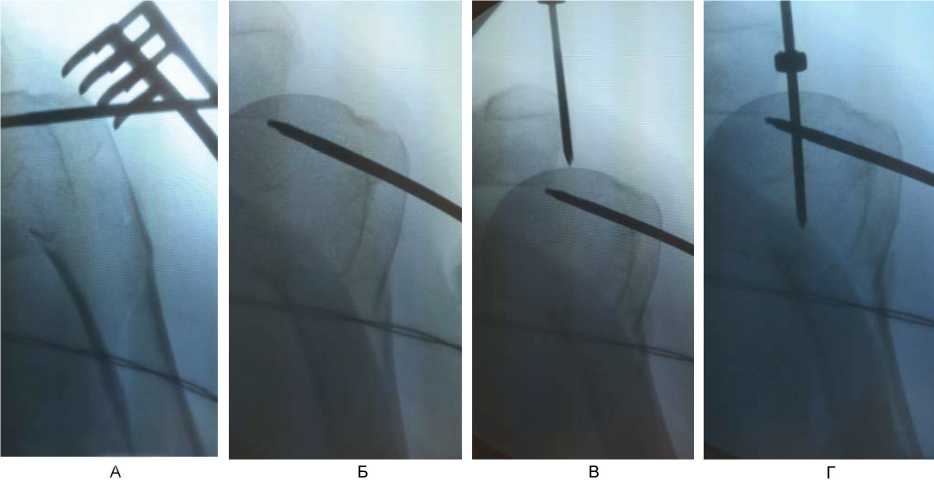

При переломах типа А и В по АО с 2020 г. по настоящее время использовали методику интрамедуллярного остеосинтеза из доступов по типу проколов (до 1 см) с применением непрямой репозиции с помощью спиц-джойстиков (рис. 4), время опреации – 31 мин.

Рис. 4. Непрямая репозиция под рентгенологическим контролем (ЭОП) с помощью спиц-джойстиков при переломах типа А и В по АО. А – установка толстой спицы-джойстика в проксимальный отломок; Б – репозиция варусного отклонения проксимального отломка; В – выбор точки для вскрытия интрамедуллярного канала плечевой кости под имплантат; Г – контроль положения направителя для вскрытия интрамедуллярного канала плечевой кости